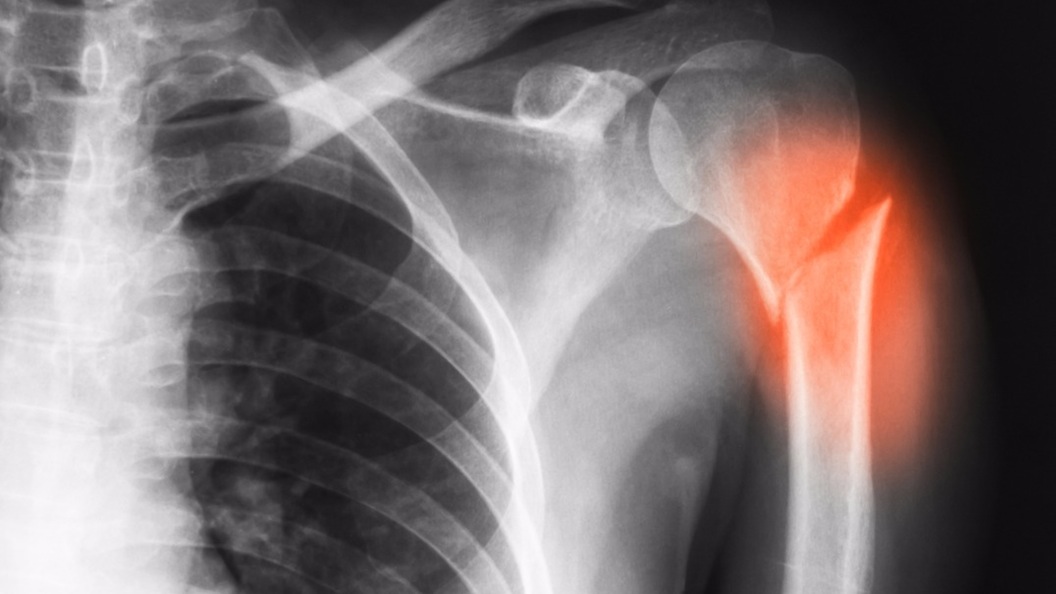

The preclinical findings come from researchers at Beaumont Hospital – Royal Oak and will be published in the journal Nanomedicine. They state that the biodegradable material could be used to heal bones in hundreds of thousands of patients requiring bone replacement, including following tumor removal, spinal fusion surgery or fractures.